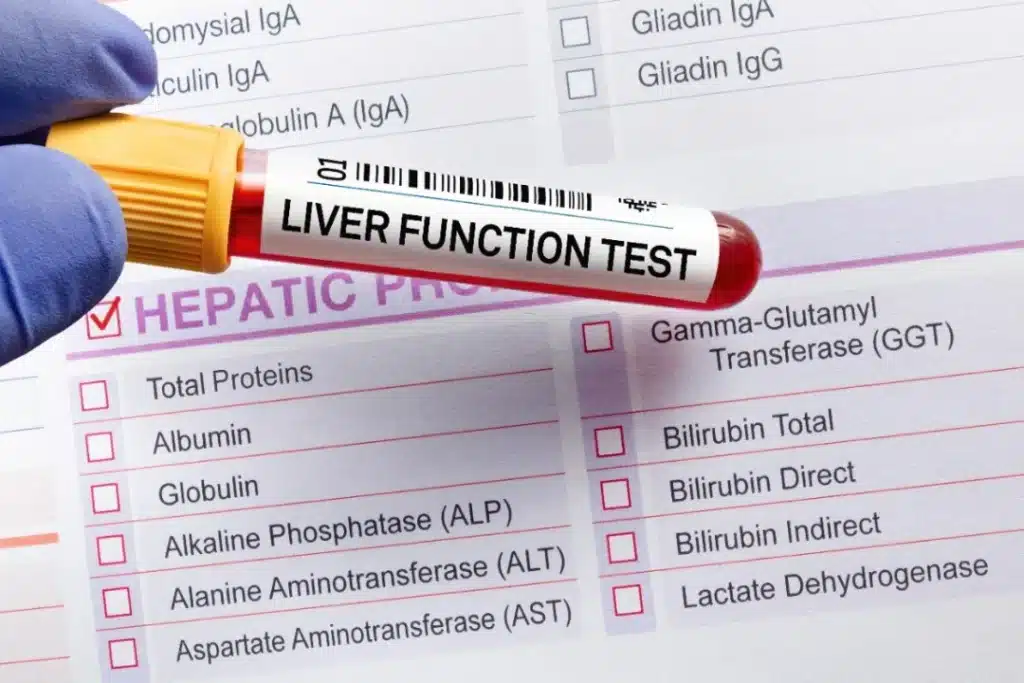

Fatty liver can go undiagnosed for years as it usually does not cause pain or other symptoms. One usually picks up fatty liver findings during routine blood tests.

If your results are concerning to your doctor, he/she may arrange an ultrasound of the liver. In severe cases, your doctor may refer you to a gastroenterologist who will then advise for a liver fibroscan or biopsy for further evaluation of the extent or severity of your fatty liver disease.

Your doctor will usually take your medical history and examine you physically— covering blood pressure, weight, height, waistline measurement, etc. Depending on how you fare, your cardiovascular organs and liver may also be screened.

Subsequently, blood tests which cover the general screening, and a liver function test are conducted to screen for metabolic syndrome and fatty liver disease. Depending on your individual risk factors, you may also be required to have imaging (e.g., ultrasound, CT scan, MRI) taken of your liver. You can discuss your concerns with your doctor regarding NAFLD and decide on any suitable tests for further evaluation.